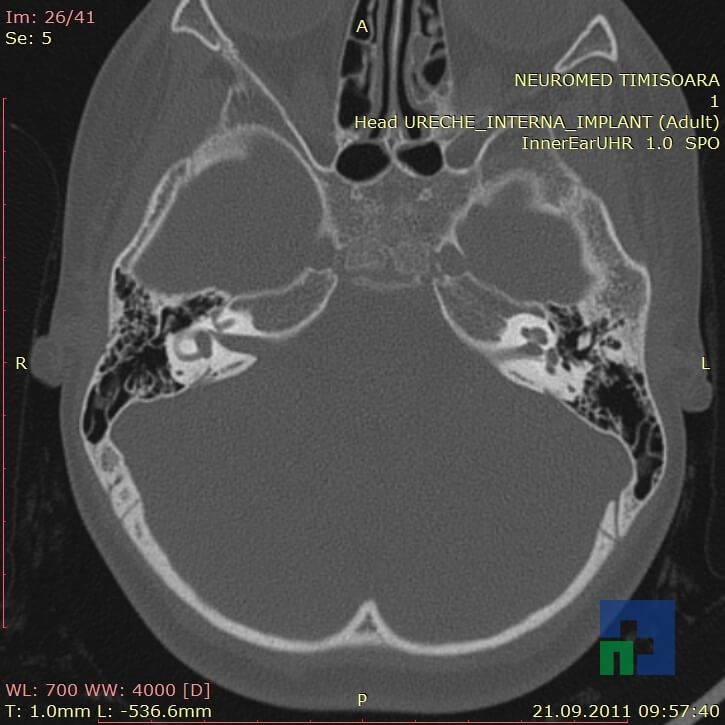

- Diagnosticul traumatismelor de bază de craniu